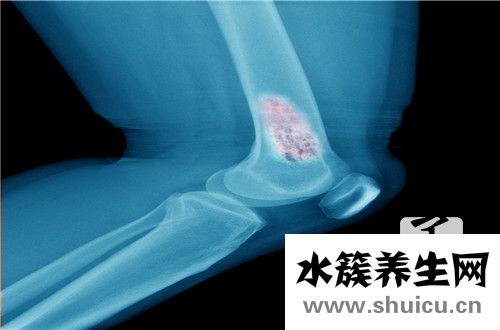

針對腓骨骨折的醫治,單純性選用內固定不動手術治療治療法會對病人造成一定的影響,如對病人部分的軟組織導致更大的損害,造成產生十分比較嚴重的手術后病發癥。運用外固定不動手術治療對腓骨骨折病人開展醫治,其骨折端平穩實際效果不佳。除此之外,外固定不動手術治療會造成病人手術后出現多種多樣欠佳病癥,如骨節粘連、肌肉僵硬及功能問題等。近些年選用內外固定不動融合的治療法對腓骨骨折病人開展醫治,選用部分割開的方法,對蔓延到關節面的骨折注視下開展復位,部分內開展固定不動,另外選用骨外固定夾板開展外固定不動,具備固定不動跨距大、偶然性強等特性。根據選用內外固定不動融合療法治療腓骨骨折,既可以使病人骨折位置的可靠性明顯提高,另外可以顯著降低病人手術后病發癥的概率。從而可以合理地防止保守治療與單純性內固定不動的各種各樣缺點,減少了病人承擔的手術治療痛楚。